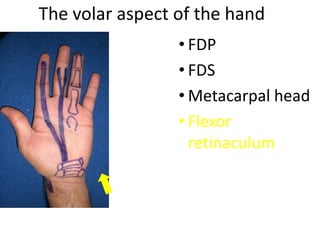

- Naming the bones, joints, tendons, nerves and skin landmarks of the hand and wrist.

- It describes flexor tendon zones, extensor compartments, and pulley system anatomy.